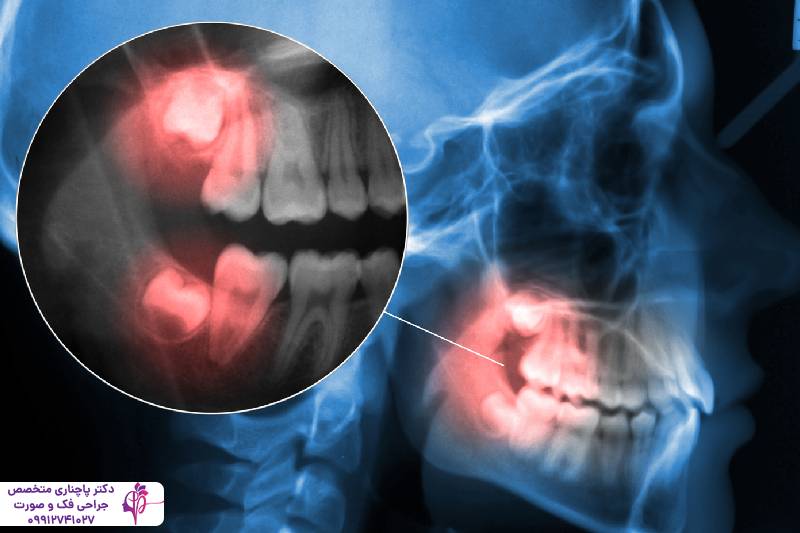

دندان عقل فک پایین نزدیکترین دندان به گلو و دندان عقل فک بالا نزدیکترین دندان به مفصل فک و سینوسهاست به همین دلیل میتواند باعث درد مستقیم در گوش، گلو، گردن و حتی پشت چشم شود. به این پدیده درد ارجاعی گفته میشود. یعنی گاهی مغز نمیتواند دقیقا محل اصلی درد را تشخیص دهد و آن را به نواحی دیگر نسبت میدهد. برای همین خیلی افراد بدون اینکه بدانند منشا اصلی این درد کجاست ماهها قطره گوش، اسپری گلو یا آنتیبیوتیکهای بیفایده استفاده میکنند. در حالی که فقط یک عکس ساده کافیست تا مشکل دندان عقل و منشا اصلی درد مشخص شود.

درمان گوش درد و گلودرد ناشی از دندان عقل بستگی به علت دارد. اول از همه دندانپزشک باید با عکس میزان نهفته بودن یا شدت عفونت را بررسی کند. اگر دندان کاملا نهفته باشد بهترین راه کشیدن آن است. این عمل می تواند ارتباط درد گوش یا گلو با دندان عقل را از بین ببرد. برای تسکین موقت شستن دهان با آب و نمک گرم، کمپرس سرد و مصرف مسکن پیشنهاد میشود.